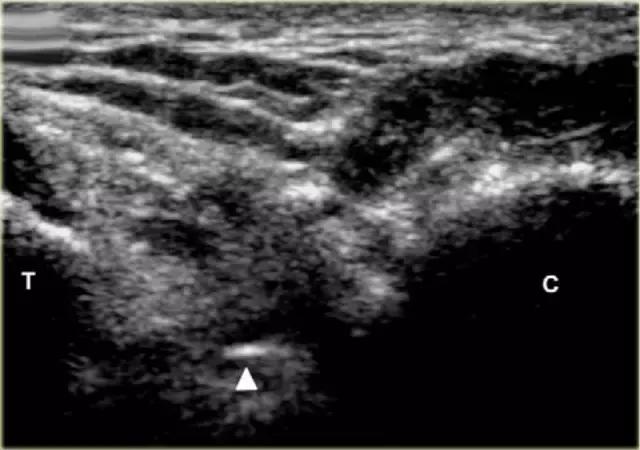

使用超声波可以容易地视察窦性骨壁。患者转向对侧,将待治疗的足以其内侧表面靠在桌面上,脚的外侧位于最上面。探头保持在关于脚的冠状平面中。

在跗骨窦被识别为跟骨的前处理和距骨颈之间的三角空间。针(箭头)的前端的锥形跗骨窦,这是由距骨(T)和跟骨(C)的边界内可以看到。

根据炎症的程度,可能存在空间的充血,并且可能存在中间血管可见,这是人们希望避免的。但是这又是比较容易的,特别是彩色多普勒。